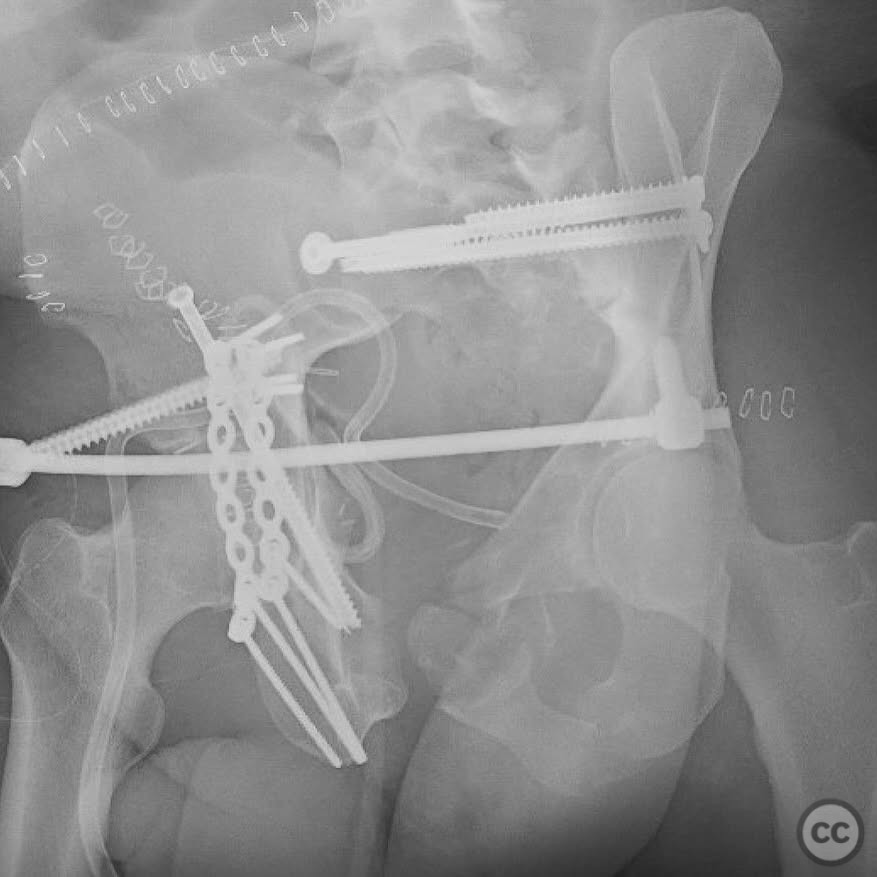

Clinical and radiological findings:  The patient presented with a highly unstable pelvic ring injury and a transverse acetabulum fracture, accompanied by a bladder injury. The bladder injury was addressed emergently with a low vertical midline Pfannenstiel incision for repair, followed by the placement of a low right-sided suprapubic catheter. Radiological imaging confirmed the transverse acetabular fracture and disruption of the left sacroiliac joint, along with a displaced sacral fracture.

Planning remarks:  The preoperative plan involved a staged approach to address the combined injuries. Initially, the focus was on stabilizing the pelvic ring to provide a stable base for subsequent acetabular reconstruction. The left sacroiliac joint disruption was to be reduced and stabilized first, followed by lag screw fixation of the displaced sacral fracture. Additional screws were planned as anatomical corridors allowed. An external fixator was considered to support the posterior ring stabilization. The second stage involved open reduction and internal fixation (ORIF) of the acetabulum through a Kocher-Langenbeck approach, with potential anterior column fixation via the modified Stoppa approach if necessary.

Orthopaedic implants used:   Lag screws for sacroiliac joint and sacral fracture fixation, external fixator for posterior ring stabilization, potential plate and screw constructs for acetabular ORIF through Kocher-Langenbeck and modified Stoppa approaches.